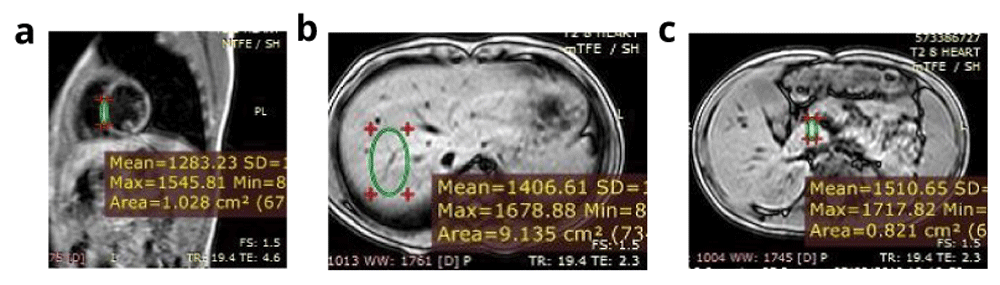

In total, 40 βTM, 20 SCD and 60-age and sex matched subjects were included in the study. The study group consisted of 33 (55%) men and 27 (45%) women. Their mean age was 13.7 (±4.4) years and mean age at diagnosis was 12.4 (±8.6) months. A total of 40 (66.7%) patients were splenectomised (33 with βTM and 7 with SCD), and 58 patients (96.7%) were receiving a chelator (39 βTM; 19 SCD; p=0.6) for a duration ranging from 6 to 120 month (median 48 months). Assessment of the iron overload status of the studied patients revealed that 34 (56.7%) patients had average serum ferritin exceeding 2500 ng/ml, 10 (16.7%) had LIC ≥7 mg Fe/g dry liver weight (dw), 20 patients (33.3%) showed mild pancreatic iron overload and only one patient had evidence of cardiac iron overload of moderate severity (Figure 1). Other demographic and laboratory data are illustrated in Table 1.

a) Calculated myocardial T2* equals 13.3 ms and myocardial iron concentration equals 1.91 mg/g (moderate cardiac iron overload). b) Calculated hepatic T2* equals 26.5 ms and liver iron concerntration equals 0.60 mg /g (no hepatic iron overload). c) Calculated pancreatic T2* equals 40 ms (no pancreatic iron overload). Conclusion: The patient has moderate cardiac iron overload, normal hepatic and pancreatic iron concentration.